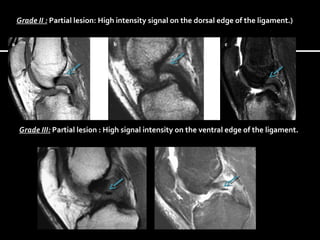

Grade II : Partial lesion: High intensity signal on the dorsal edge of the ligament.)

Grade III: Partial lesion : High signal intensity on the ventral edge of the ligament.

Grade II :Partial lesion: High intensity signal on the dorsal edge of the ligament.) Grade III: Partial lesion : High signal intensity on the ventral edge of the ligament.